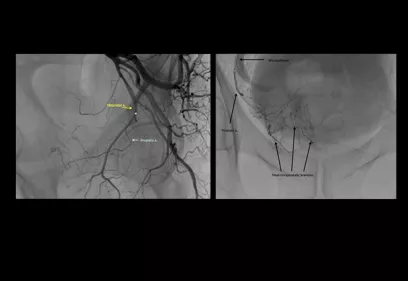

Cover image of a body scan of IMAGES magazine

IMAGES

Images is an annual publication on milestones and progress in radiology.

Read the latest issue